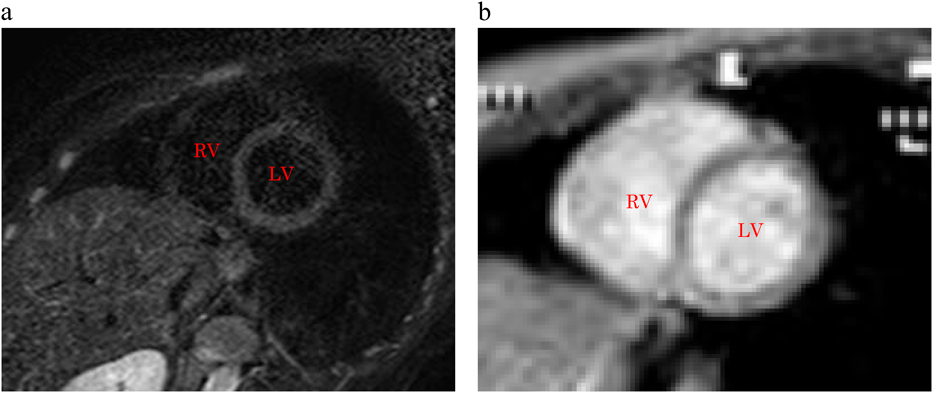

発症後33日目に運動負荷心筋シンチグラフィーと心臓MRI検査を施行した(Fig. 4a, b).テトロフォスミンによる運動負荷心筋シンチグラフィーでは,心筋虚血を示唆する所見は認めなかった.MRIではT2で高信号領域は認めず,心筋の浮腫や遅延造影での高信号領域はなく,心筋炎を疑う所見は認めなかった.その後の検査でも心筋炎を疑うウイルス抗体値の上昇はなく,MRIで心筋炎を示唆する所見が乏しかったことから,CSAと診断した.薬物治療に関しては,発作予防薬の必要性を説明したが両親の承諾が得られなかったため行わず,硝酸薬を常時携帯して発作時に舌下投与を行うよう指示した.現在,胸痛発作から2年が経過したが再発はない.CSA再発時には冠攣縮薬物誘発試験を行い,発作予防薬の導入を検討することにしている.

Pediatric Cardiology and Cardiac Surgery 37(4): 307-311 (2021)

Fig. 4 MRI

a: T2-weighted MR image. b: delayed contrast image. No hyperintensity areas were detected on the T2-weighted MR and delayed contrast images. No evidence of myocarditis was found because there was no myocardial edema. LV, left ventricle; RV, right ventricle.